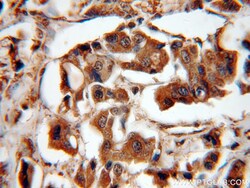

- Submitted by

- Invitrogen Antibodies (provider)

- Main image

- Experimental details

- Immunohistochemistry of paraffin-embedded human breast cancer using 14412-1-AP (PEG10 antibody) at dilution of 1:100 (under 40x lens).